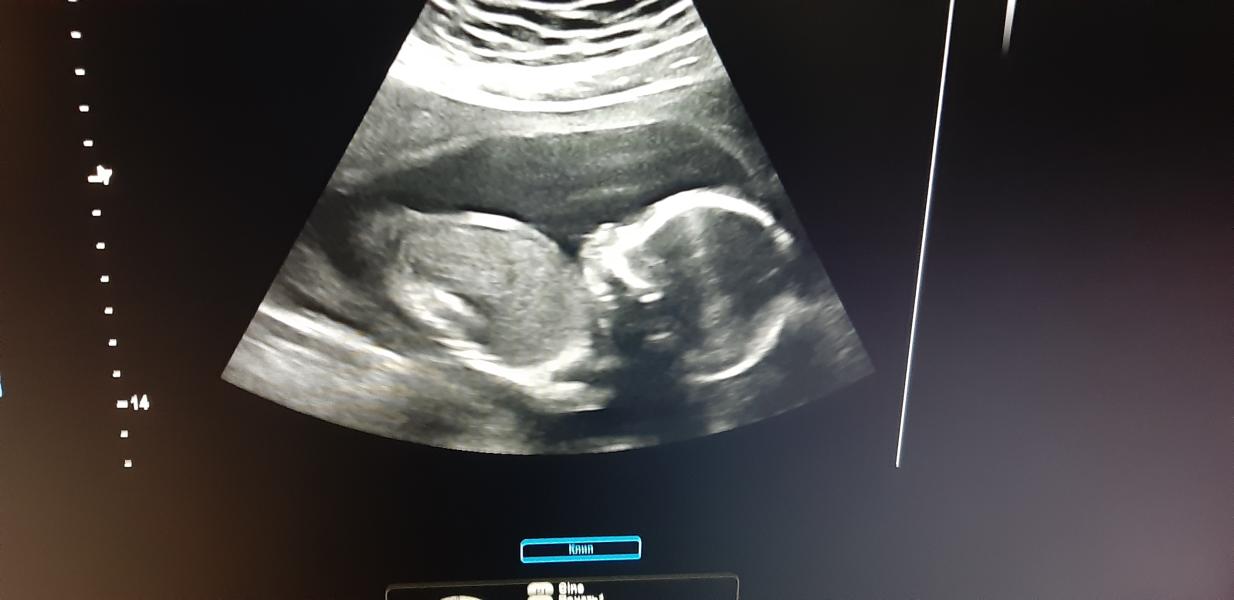

20.6 недель. Прошла 2 скрининг.Подтвердили мальчика. Вес 388 гр. Носик 5,7. Лежал спиной к датчику, час просили повернуться) Жду с нетерпением следующей встречи!!!🥰🥰🥰